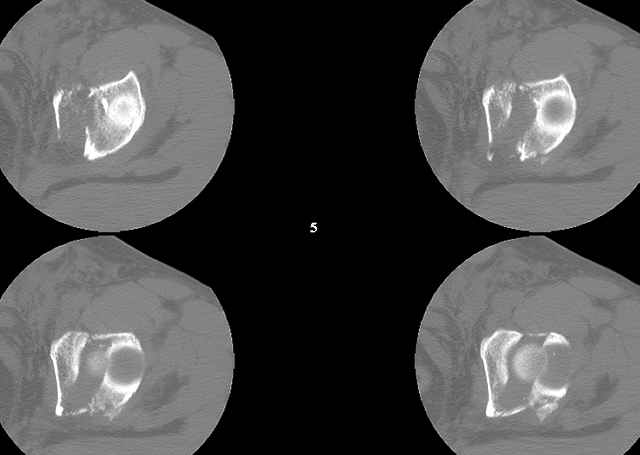

A CT scan will rarely lie to you...reveals your reduction and implants...we use it to assess, teach, grade, and try to get better next time.